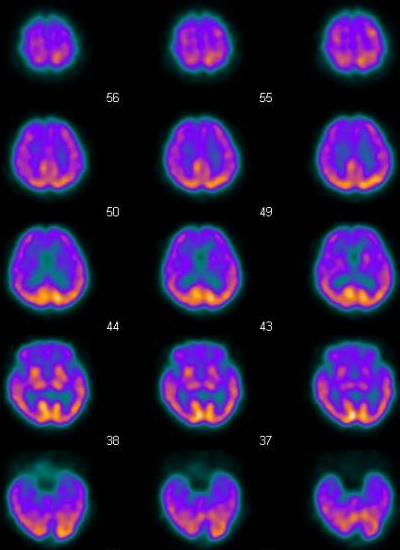

這是個歷史事件,當時的情況是,有個病人要來做Brain的perfusion,他顱內的血管有阻塞,因此可預期的在注射完ECD之後,應該可以看到腦部影像的缺損,不過如果事情都能夠發展的這麼順利,那麼科學就不會有進步了。事發的經過是這樣的,原本要注射的藥劑是Tc-99m ECD,可是不小心拿到旁邊的Tc-99m MDP,10:30注射的,接下來原本要做bone scan要打針時,就找不到Tc-99m MDP來注射,此時才發現打錯病人了,這時只好讓bone scan的病人回病房等,先緊急補叫一支MDP讓他用,接下來就必須面對這個打錯藥的病人了,我們的選擇有幾個,第一是跟病人坦承打錯藥了,請病人下次再來,同時詢問病人是否要做一次bone scan看看身體骨頭的狀況,不過坦白講,我們不喜歡這個選項,因為很有可能會讓事情發展到失控的狀況,因此我們採取了另一種方式來處理,就是請原本在外面等的病人進來,跟他說剛打針的劑量有點不夠,因此要再幫他加一點藥,坦白講這步驟還挺有風險的,於是我們替病人注射了ECD(11:00),當時我們的想法是,因為兩個藥物的分布區域並不相同,Tc-99m MDP沒有辦法穿透BBB,因此並不會干擾到腦部的影像,所以我們在刻意稍等了一下,在12:30開始做Brain的掃描,那時Tc-99m MDP在軟組織的清除也應該差不多了,照相的時候,在使用high resolusion collimator的情況下,每個頭的count數約在4~4.5 k counts,和平常相比並沒有明顯高出多少,因此理論上影響應該不會太大,從原始影像來看,就有點醜了,是一種骷顱頭加腦袋的影像合體,其實這時候就有點擔心,但是也只能硬著頭皮把影像照完,才能做下一步的決定。

結果揭曉,我放上當天與正常影像的比較圖。

| 整體count為77~82,MDP的確增加了很多count數,此外brain的影像加上了骨頭的影像,看起來就怪怪的 | 整體count為33~35,所看到的就是完全腦部的影像,左右的位置都相同,但是我忘記把影像調成一樣大了 |

| 在腦部外,可以看到略略的頭骨影像 | 正常的腦部影像 |

最後報告的影像,我們用mask盡量去除了外圍的頭骨,所以影像上看起來還可以交代得過去,但是這樣的錯誤,還是要非常小心,別再犯了。 |